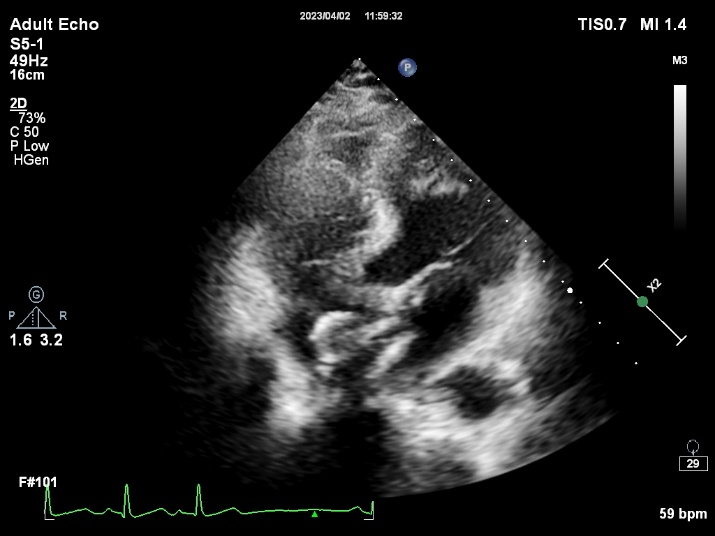

使用我国自主研发的超声引导专用介入导丝进行房间隔穿刺定位

CDS放置在二尖瓣处